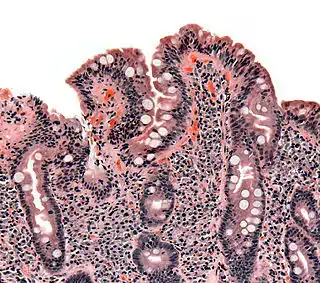

Biopsia de intestino delgado en la que se aprecia atrofia de las vellosidades intestinales, hiperplasia de las criptas y linfocitosis intraepitelial. | ||

A diferencia de los criterios habitualmente utilizados por los expertos, las lesiones que la enfermedad celiaca provoca en el intestino delgado se limitan habitualmente a la presencia de una inflamación crónica de la mucosa duodenal, constituida principalmente por linfocitos, sin atrofia de las vellosides intestinales, especialmente en los niños mayores de dos años y los adultos. Actualmente, la presencia de atrofia de las vellosidades se considera un hallazgo menos frecuente.[19][50][51][52][40][53] También en contraposición de los criterios habitualmente empleados en la práctica clínica diaria, actualmente está reconocido que la celiaquía cursa frecuentemente con serología negativa (ausencia de anticuerpos específicos en sangre), especialmente la anti-transglutaminasa.[19][50][40][54][55][56][57] Esto se debe a que la anti-transglutaminasa se produce en la mucosa del intestino y con frecuencia, permanece depositada en ella sin pasar a la sangre.[20] [26][58] [59] Su evaluación en las biopsias duodenales es un nuevo método diagnóstico, que puede ayudar a detectar la enfermedad, pero es una técnica compleja, engorrosa y cara, por lo que su empleo no está generalizado en la práctica clínica habitual.[40][60][61] Esta prueba ha sido incluida en 2018 en España, como parte del nuevo protocolo para el diagnóstico precoz de la enfermedad celíaca.[62]

Las lesiones que la celiaquía provoca en el intestino delgado de un celíaco no se limitan a la presencia de atrofia de las vellosidades intestinales, sino que con frecuencia consisten en cambios mínimos, con inflamación leve o moderada, especialmente en los niños mayores de dos años y los adultos.[19][50][51][52] [40]

Para el estudio de las biopsias duodenales, es fundamental recurrir a la utilización sistemática de la clasificación de Marsh en todos los servicios de Anatomía Patológica. Su utilización ayuda mucho al reconocimiento de casos ocultos y dudosos, permite emplear un lenguaje común, clasificar mejor los hallazgos y comprender que no es imprescindible la presencia de atrofia vellositaria para confirmar el diagnóstico, pues, como sucede con los síntomas, el espectro morfológico de las lesiones duodenales es muy amplio.[19][27]

Hallazgos en las biopsias duodenales

El contacto del intestino con el gluten conduce a la aparición de un daño en la mucosa del intestino delgado que no se limita, como tradicionalmente se pensaba, a la atrofia de las vellosidades intestinales, sino que incluye una serie de cambios inflamatorios que son mucho más frecuentes que aquella. Las lesiones abarcan desde casos en los que únicamente se aprecia un aumento de la población de linfocitos intraepiteliales (enteritis linfocítica) hasta formas avanzadas de atrofia vellositaria.[19][50] Cualquiera de estas lesiones, incluso las formas más leves, puede cursar con diversos estados carenciales, incluyendo anemia, osteopenia u osteoporosis, y un amplio abanico de síntomas digestivos y extradigestivos;[19][50] y presentan riesgo de complicaciones importantes a largo plazo si permanecen sin diagnosticar ni tratar, incluyendo un aumento moderado de la mortalidad.[156]

Dado que las lesiones histológicas pueden ser parcheadas, se aconseja la toma de al menos 4 muestras para el análisis histológico. El resultado del estudio anatomopatológico permite confirmar la existencia de lesiones compatibles y establecer el estadio de la lesión (Clasificación de Marsh). El espectro de lesiones histológicas que presentan estos pacientes es amplio y oscila desde formas de enteritis linfocíticas, donde únicamente se encuentra un incremento de la población de linfocitos intraepiteliales (>25 %) [Marsh 1], hasta formas de atrofia grave de la mucosa [Marsh 3]. Es importante disponer de inmunotinciones para llevar a cabo el contaje de linfocitos intraepiteliales, cuando las tinciones con hematoxilina-eosina no son concluyentes. Solo de este modo pueden diagnosticarse con razonable seguridad las formas de enteritis linfocítica (>25 linfocitos/100 células epiteliales).

A partir de la edad de 2 años, las formas con atrofia de vellosidades disminuyen notablemente, ya que predominan las presentaciones con solo inflamación (infiltración de linfocitos o enteritis linfocítica), que son las que producen bajos niveles de anticuerpos en sangre.

Los hallazgos de la biopsia duodenal deben ser interpretados con detalle por un patólogo experto, e interesado en el diagnóstico de esta enfermedad, siguiendo los criterios de Marsh modificados, que clasifica esta enfermedad en 4 tipos o estadios. Se puede tener una enfermedad celíaca con biopsia duodenal con solo un aumento en el porcentaje de linfocitos intraepiteliales o una duodenitis crónica (estadio 1 o infiltrativo, de dicha clasificación).

La observación al microscopio tras tinción de las muestras extraídas, mediante hematoxilina-eosina e inmunohistoquímica con marcadores específicos para teñir los linfocitos CD3, permite analizar la histología y el número y distribución de los linfocitos intraepiteliales.

Su cuantificación ayuda a conocer mejor el grado de lesión según el sistema más utilizado actualmente, como son los “criterios de Marsh” descritos en 1992[158] y revisados por Oberhüber en 1996.

Esta clasificación anatomopatológica de las biopsias duodenales debe emplearse de forma rutinaria para el estudio de las muestras. Se utiliza ampliamente en todo el mundo y ha demostrado de sobras su gran utilidad diagnóstica y el amplio espectro de alteraciones histológicas existentes en la celiaquía, que van desde una mucosa normal o con cambios mínimos hasta la atrofia de las vellosidades intestinales.

Según estos criterios, además de la atrofia de vellosidades, aparecen estas lesiones:

- Lesión tipo Marsh 0. Cambios preinfiltrativos.

- Lesión tipo Marsh 1. Se observan 20 o 25 linfocitos intraepiteliales (depende de la técnica de tinción) por cada 100 enterocitos. Se expresa mediante porcentaje. Es decir, se considera Marsh 1 cuando la infiltración linfocitaria (LIES) es superior al 20 % o 25 %. Esta enteritis linfocítica es el hallazgo histológico más habitual en la enfermedad celíaca del adulto y niño mayor de 2 años.

- Lesión tipo Marsh 2. Se observa el patrón anterior además de hiperplasia de criptas (están en la base de las vellosidades).

- Lesión tipo Marsh 3. Se observa el patrón anterior y además existe acortamiento (atrofia) de vellosidades. Se subdivide en:

- - Marsh 3a, si es parcial o leve;

- - Marsh 3b, si es subtotal;

- - Marsh 3c, si es total.